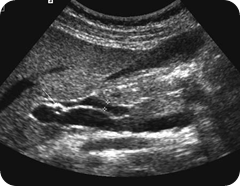

Ultrasound Diagnosis Of Common Bile Duct Dilatation

Ultrasound Diagnosis of Common Bile Duct Dilatation1 Timothy G. Lee, M.D., Sidney C. Henderson, M.D.,2 and Robert Ehrlich, M.D. (CBD) shows its characteristic shape. In this scan, the portal vein (PV) is seen in its cross section. ... Fetch Full Source